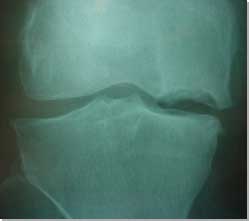

Radiographs of the knee are usually the first imaging studies, especially if bone wear and tear is suspected clinically. Weight-bearing radiographs are helpful in assessing the extent of arthritis in the knee joint and in planning various joint resurfacing procedures.

| Osteochondral

defect (OCD) of the medial femoral condyle. |

Radiographs are often required after acute knee trauma. If the trauma is severe, and the injured person complains of severe pain and inability to bear weight, fractures must be ruled out. Anterioposterior and lateral radiographs of the knee best visualise the tibio-femoral and tibio-fibular joints. The skyline, or tangential, view allows the assessment of the patellofemoral joint and provides an unobstructed view of the patella. Stress radiographs (the knee is forced manually into varus or valgus position) can demonstrate ligament deficiency, but this technique is rarely used nowadays.